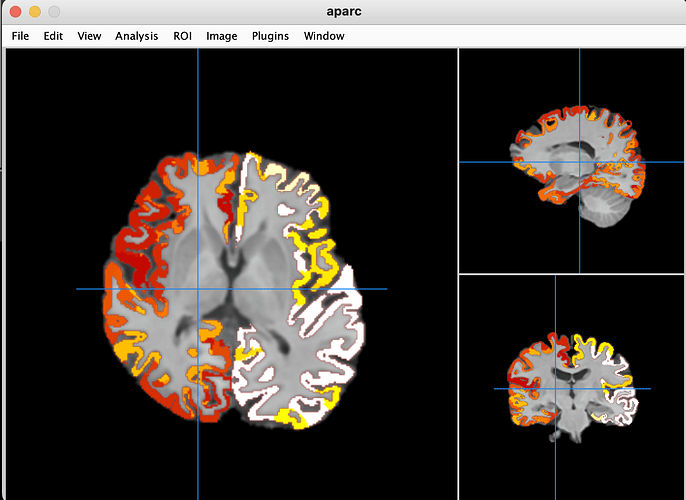

The Freesurfer segmentation file aparc.a2009s+aseg_REN_all.nii.gz appears to align well with anatSS.sub-ep069_anat.nii when viewed in Mango which I assume applies a deoblique transformation automatically.

However, it is not the case when I overlay copy_af_FS_EN_anat on anatSS.sub-ep069 in AFNI